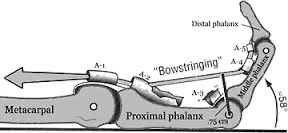

Great presentation and discussion on surgical site marking in hand surgery by Riikka Silversten, part of her dissertation for Orthopaedics MSc UCL. Hand surgeon in the making!! IFSSH FESSH British Society for Surgery of the Hand UCLH #ILookLikeASurgeon